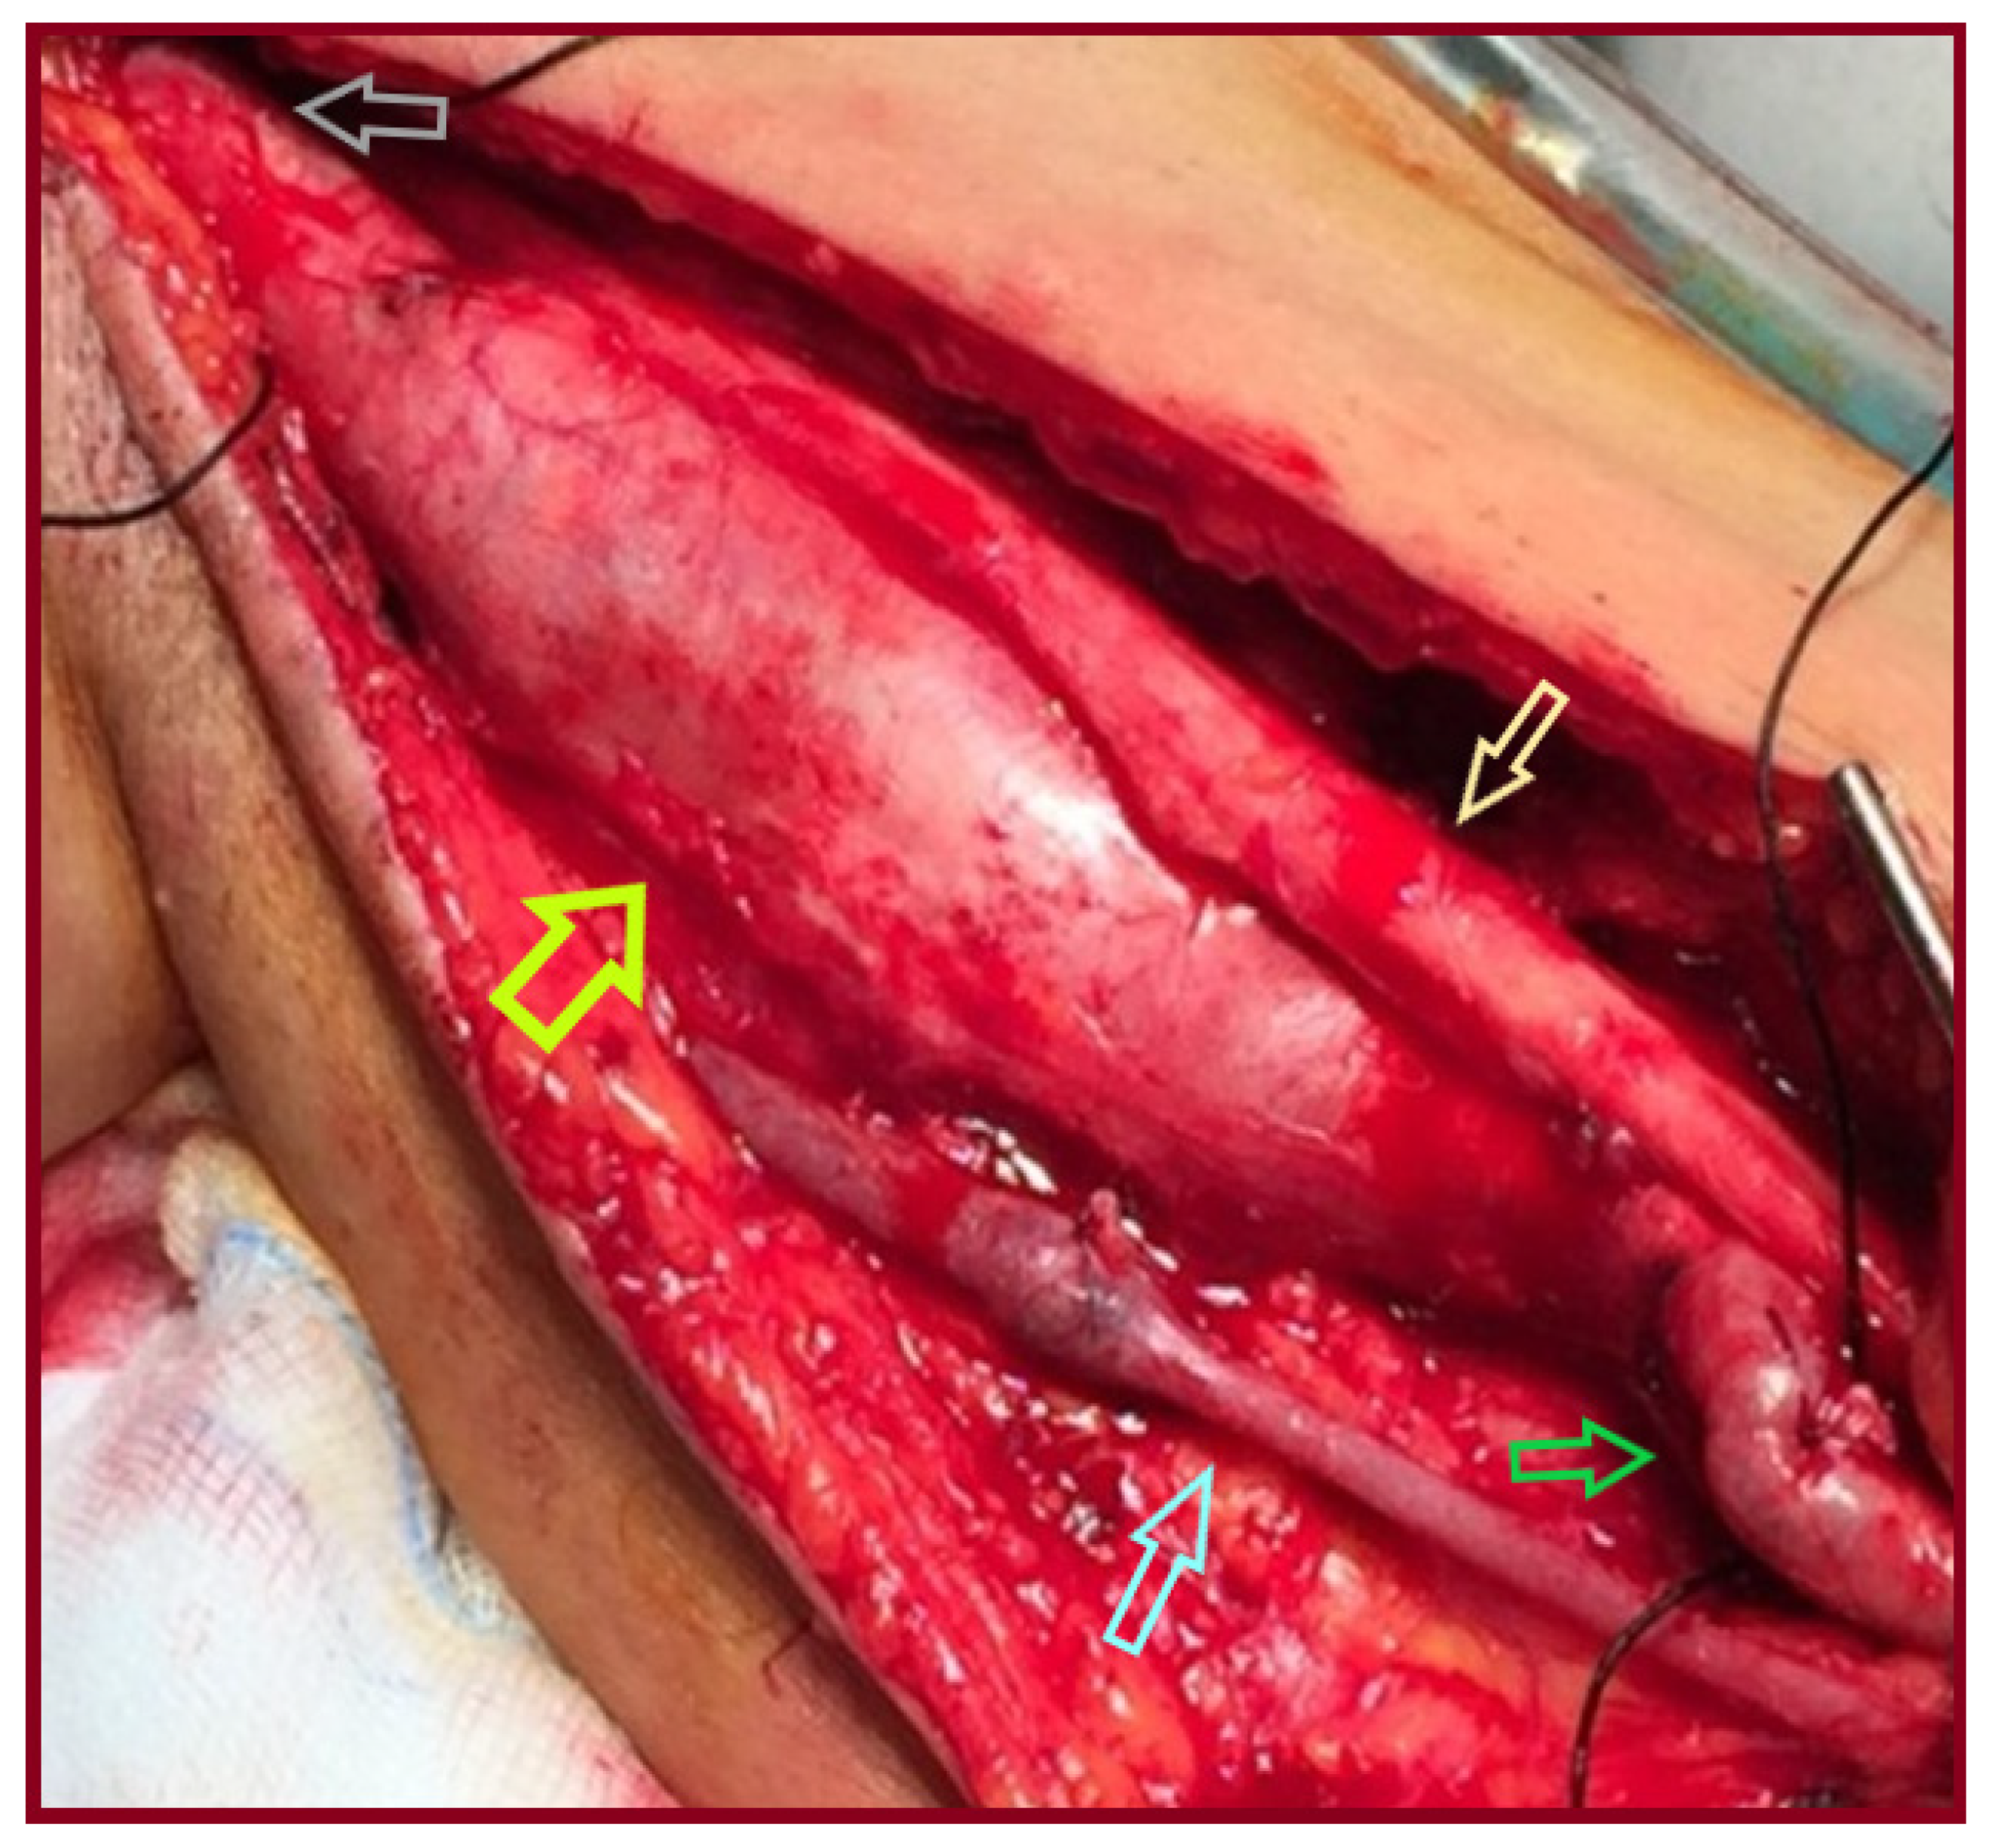

| 1/ 2001 | 28/M | No/ Palpable mass | R/Distal third of BA, extending to ulnar artery | 3.5 | Aneurysm excision & reversed BV interposition between BA & RA, UA ligation | NA |

| 2/ 2007 | 46/M | No/ Palpable mass | L/ Distal half of BA | 4 | Aneurysm excision & reversed BV interposition | NA |

| 3/ 2015 | 65/M | No/ Palpable mass | L/ Two proximal thirds of BA | 4 | Aneurysm excision & reversed BV interposition | NA |